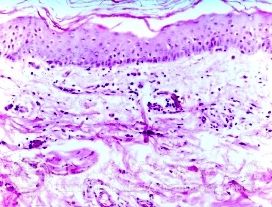

北京京城皮肤医院指出,皮肤微*对急性发作湿疹有致病作用。

有学者报道在非特应性急性发作湿疹皮炎患者皮损中总的金黄色葡萄球菌检出率为31.6 ,总的细菌检出率为70.6 ,在金黄色葡萄球以外的细菌中,表皮葡萄球菌占62.7 ,溶血型链球菌占1.7 ,其他球菌占19.6 ,杆菌占5.1 。